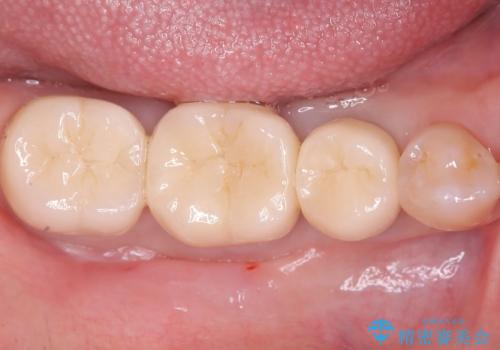

- 金属を外してセラミックを入れたいことを主訴に来院された患者さんです。

セラミックインレーにて修復を行いました。

当院でのセラミックインレーは、ラバーダムを使用して装着しております。